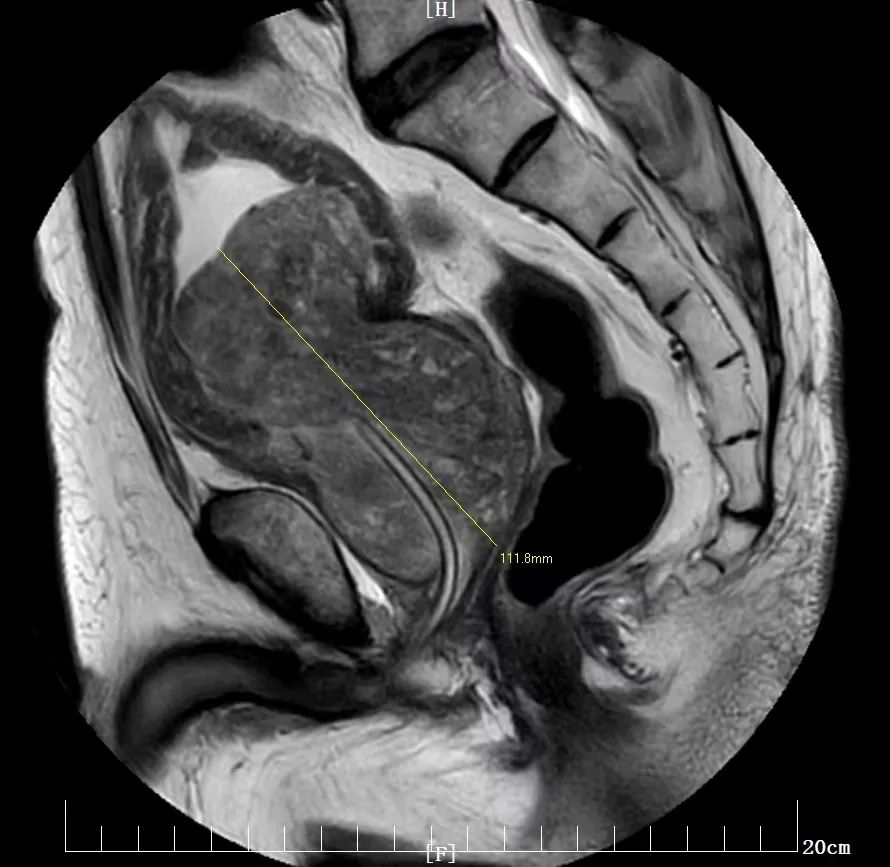

11 月 9 日,柳爷爷前往西安高新医院泌尿外科治疗。详细查体显示,柳爷爷前列腺体积显著增大至 112×80×70 mm,梗阻明显、排尿困难,仅凸入膀胱内的前列腺增生部就有 60x61x50 mm。